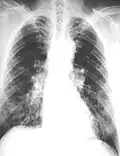

The abnormal chest x-ray and its interpretation remain the most important factors in establishing the presence of pulmonary fibrosis.[11] The findings usually appear as small, irregular parenchymal opacities, primarily in the lung bases. Using the ILO Classification system, "s", "t", and/or "u" opacities predominate. CT or high-resolution CT (HRCT) are more sensitive than plain radiography at detecting pulmonary fibrosis (as well as any underlying pleural changes). More than 50% of people affected with asbestosis develop plaques in the parietal pleura, the space between the chest wall and lungs. Once apparent, the radiographic findings in asbestosis may slowly progress or remain static, even in the absence of further asbestos exposure.[26] Rapid progression suggests an alternative diagnosis.

Extensive fibrosis of pleura and lung parenchyma

61-year-old working industrially with asbestos for decades